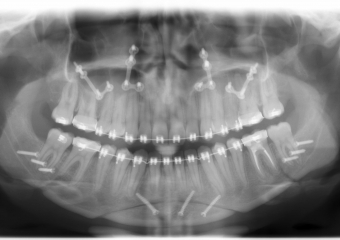

Rx Panoramico após a cirurgia  - Clínica Cliniface

Rx Panoramico após a cirurgia